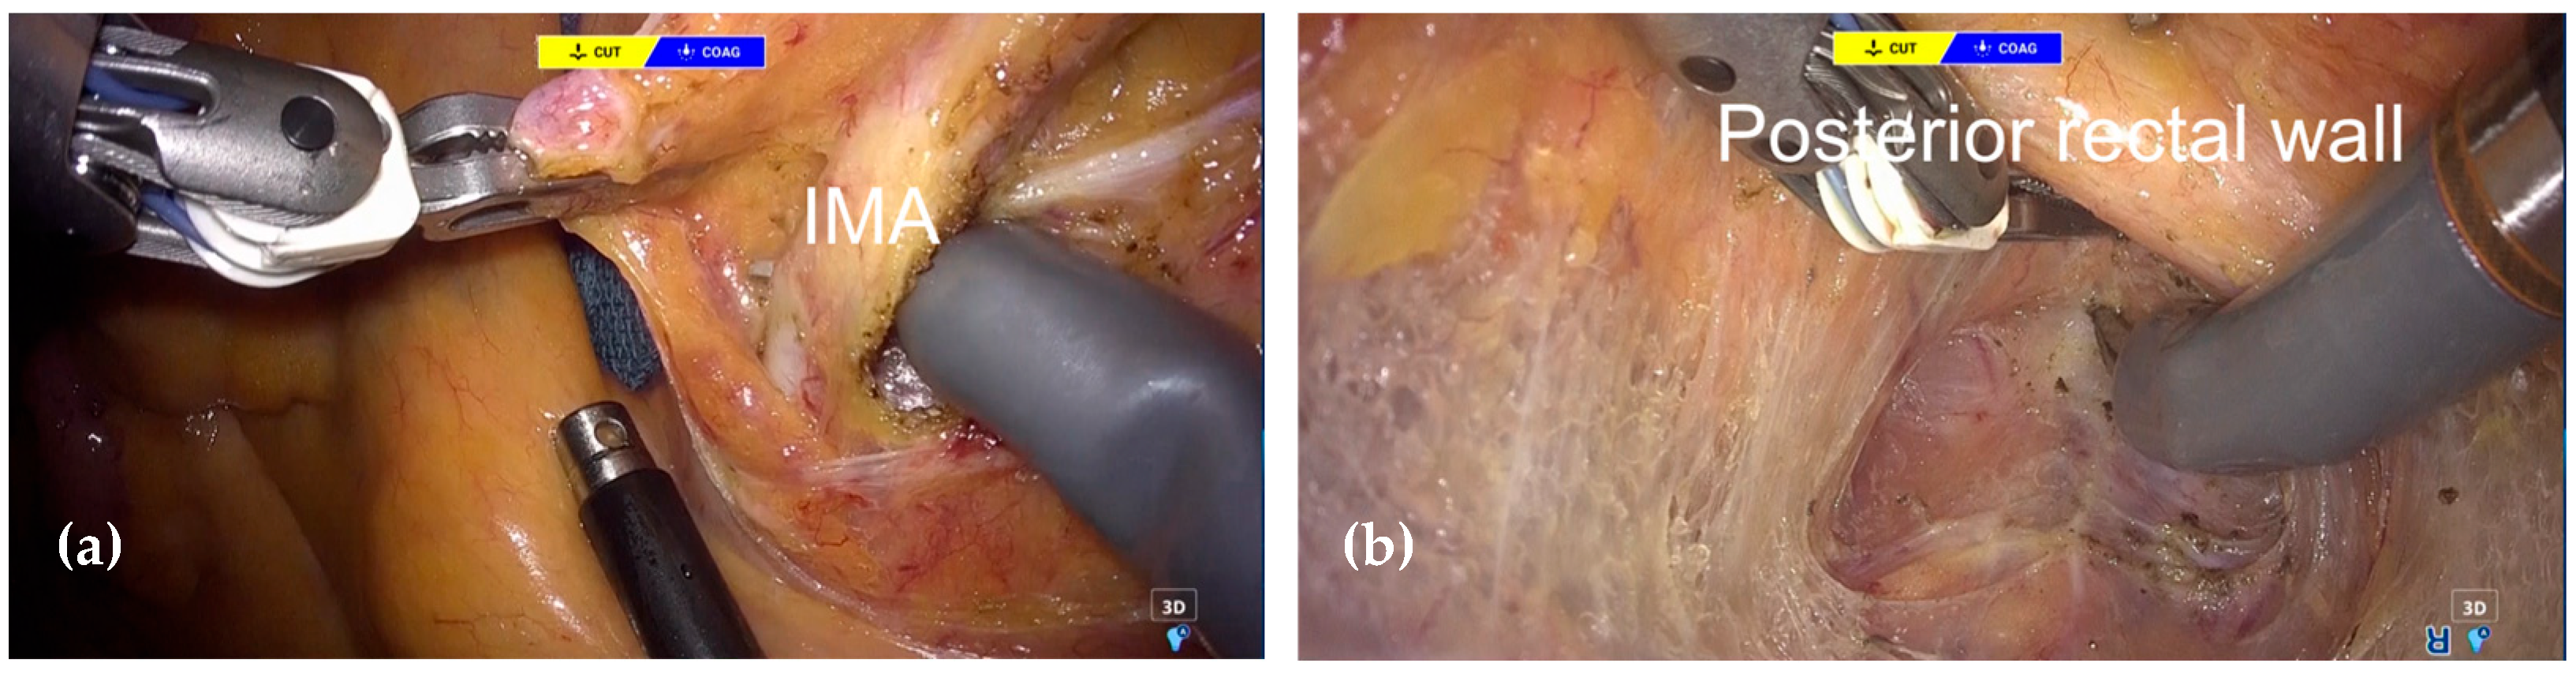

2.3. Surgical Procedure